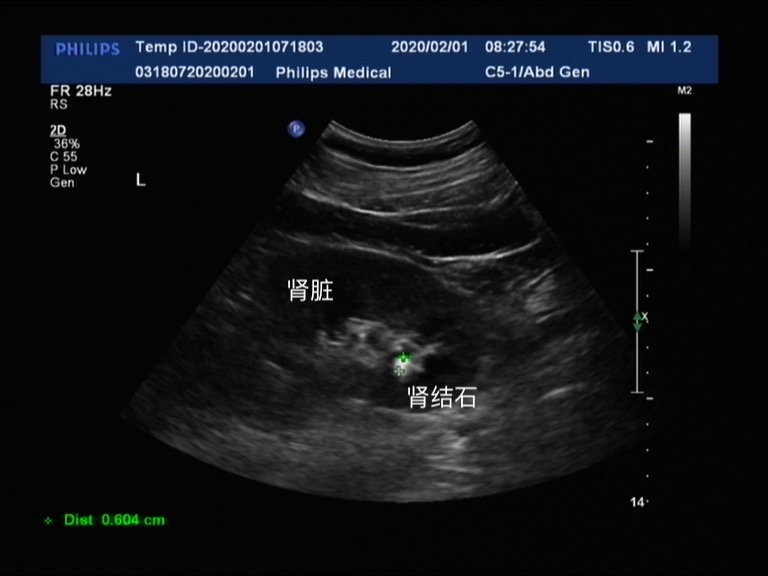

从彩超上我们可以看到,这是一个体检的肾脏彩超,其中高亮呈白色的就是肾结石。彩超通常由探头(相控阵、线阵、凸阵、机械扇扫、三维探头、内窥镜探头等)、超声波发射/接收电路、信号处理和图像显示等部分组成,所以结石在彩超上的表现是一种高亮信号。这个结石的大小是0.604cm。那么这种结石需要处理吗?

需要处理的结石主要是急性梗阻导致肾脏积水的结石,单纯的肾结石往往不会引起肾脏积水,也就不会引起肾功能的损伤,所以较小的肾结石是不需要特殊处理的。一般建议就是多饮水,以及控制饮食,避免结石进一步长大,以及避免结石从肾脏掉入输尿管内。就拿上面这个结石来说,0.6cm的肾结石在肾脏内是不会引起任何症状的,但是当它脱落掉入输尿管中是,相对于输尿管的管径,这就是一个大石头了,会导致输尿管的梗阻,引起剧烈腰痛以及肾功能的损伤,那么这个时候它就需要积极处理了。